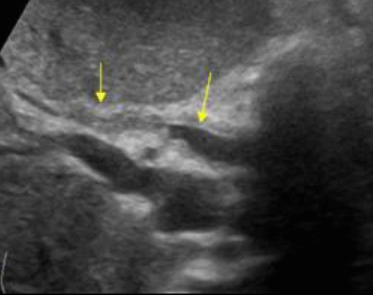

Choledocholithiasis US finding

- 총담관 내에 후방음향음영을 동반한 강한 에코가 관찰된다.

- 총담관의 확장 소견이 보인다. ( 7mm 이상)

- 담석이 관찰되지 않고 간외, 간내담관의 확장소견을 시사하는 엽총징후(shotgun sign)이나 평행관 징후(parallel channel sign)가 관찰되기도 한다.

- 엽총징후(shotgun sign): 간외 담관이 확장되어 간외 담관과 문맥이 이웃해 관찰된다.

- 평행관 징후(parallel channel sign): 간내 담관이 확장되어 인접하고 있는 문맥과 나란히 2개의 관상구조로 나타난다.